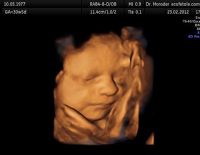

Thai 21 tuần siêu âm 4D có nên hay không mẹ nên biết

Thai 21 tuần siêu âm 4D có nên hay không là điều mà nhiều mẹ bầu thắc mắc trước khi thực hiện thủ thuật siêu âm hiện đại này. Nếu đây cũng là thắc mắc của bạn thì hãy cùng lắng nghe ý kiến của...